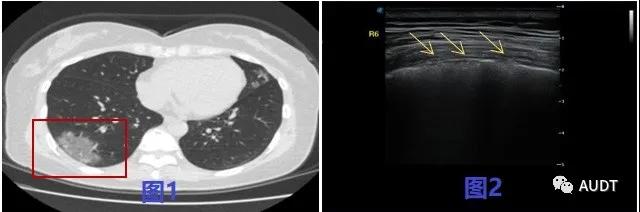

进展早期,图1 CT显示右肺下叶团片状渗出影;图2 线阵探头显示相应位置胸膜线毛糙,厚度变薄。图3双肺多发斑片渗出影,中外带为主;图4 线阵探头显示相应肺周宽大B线,胸膜凹陷,欠光滑(黄色箭头所示) 。